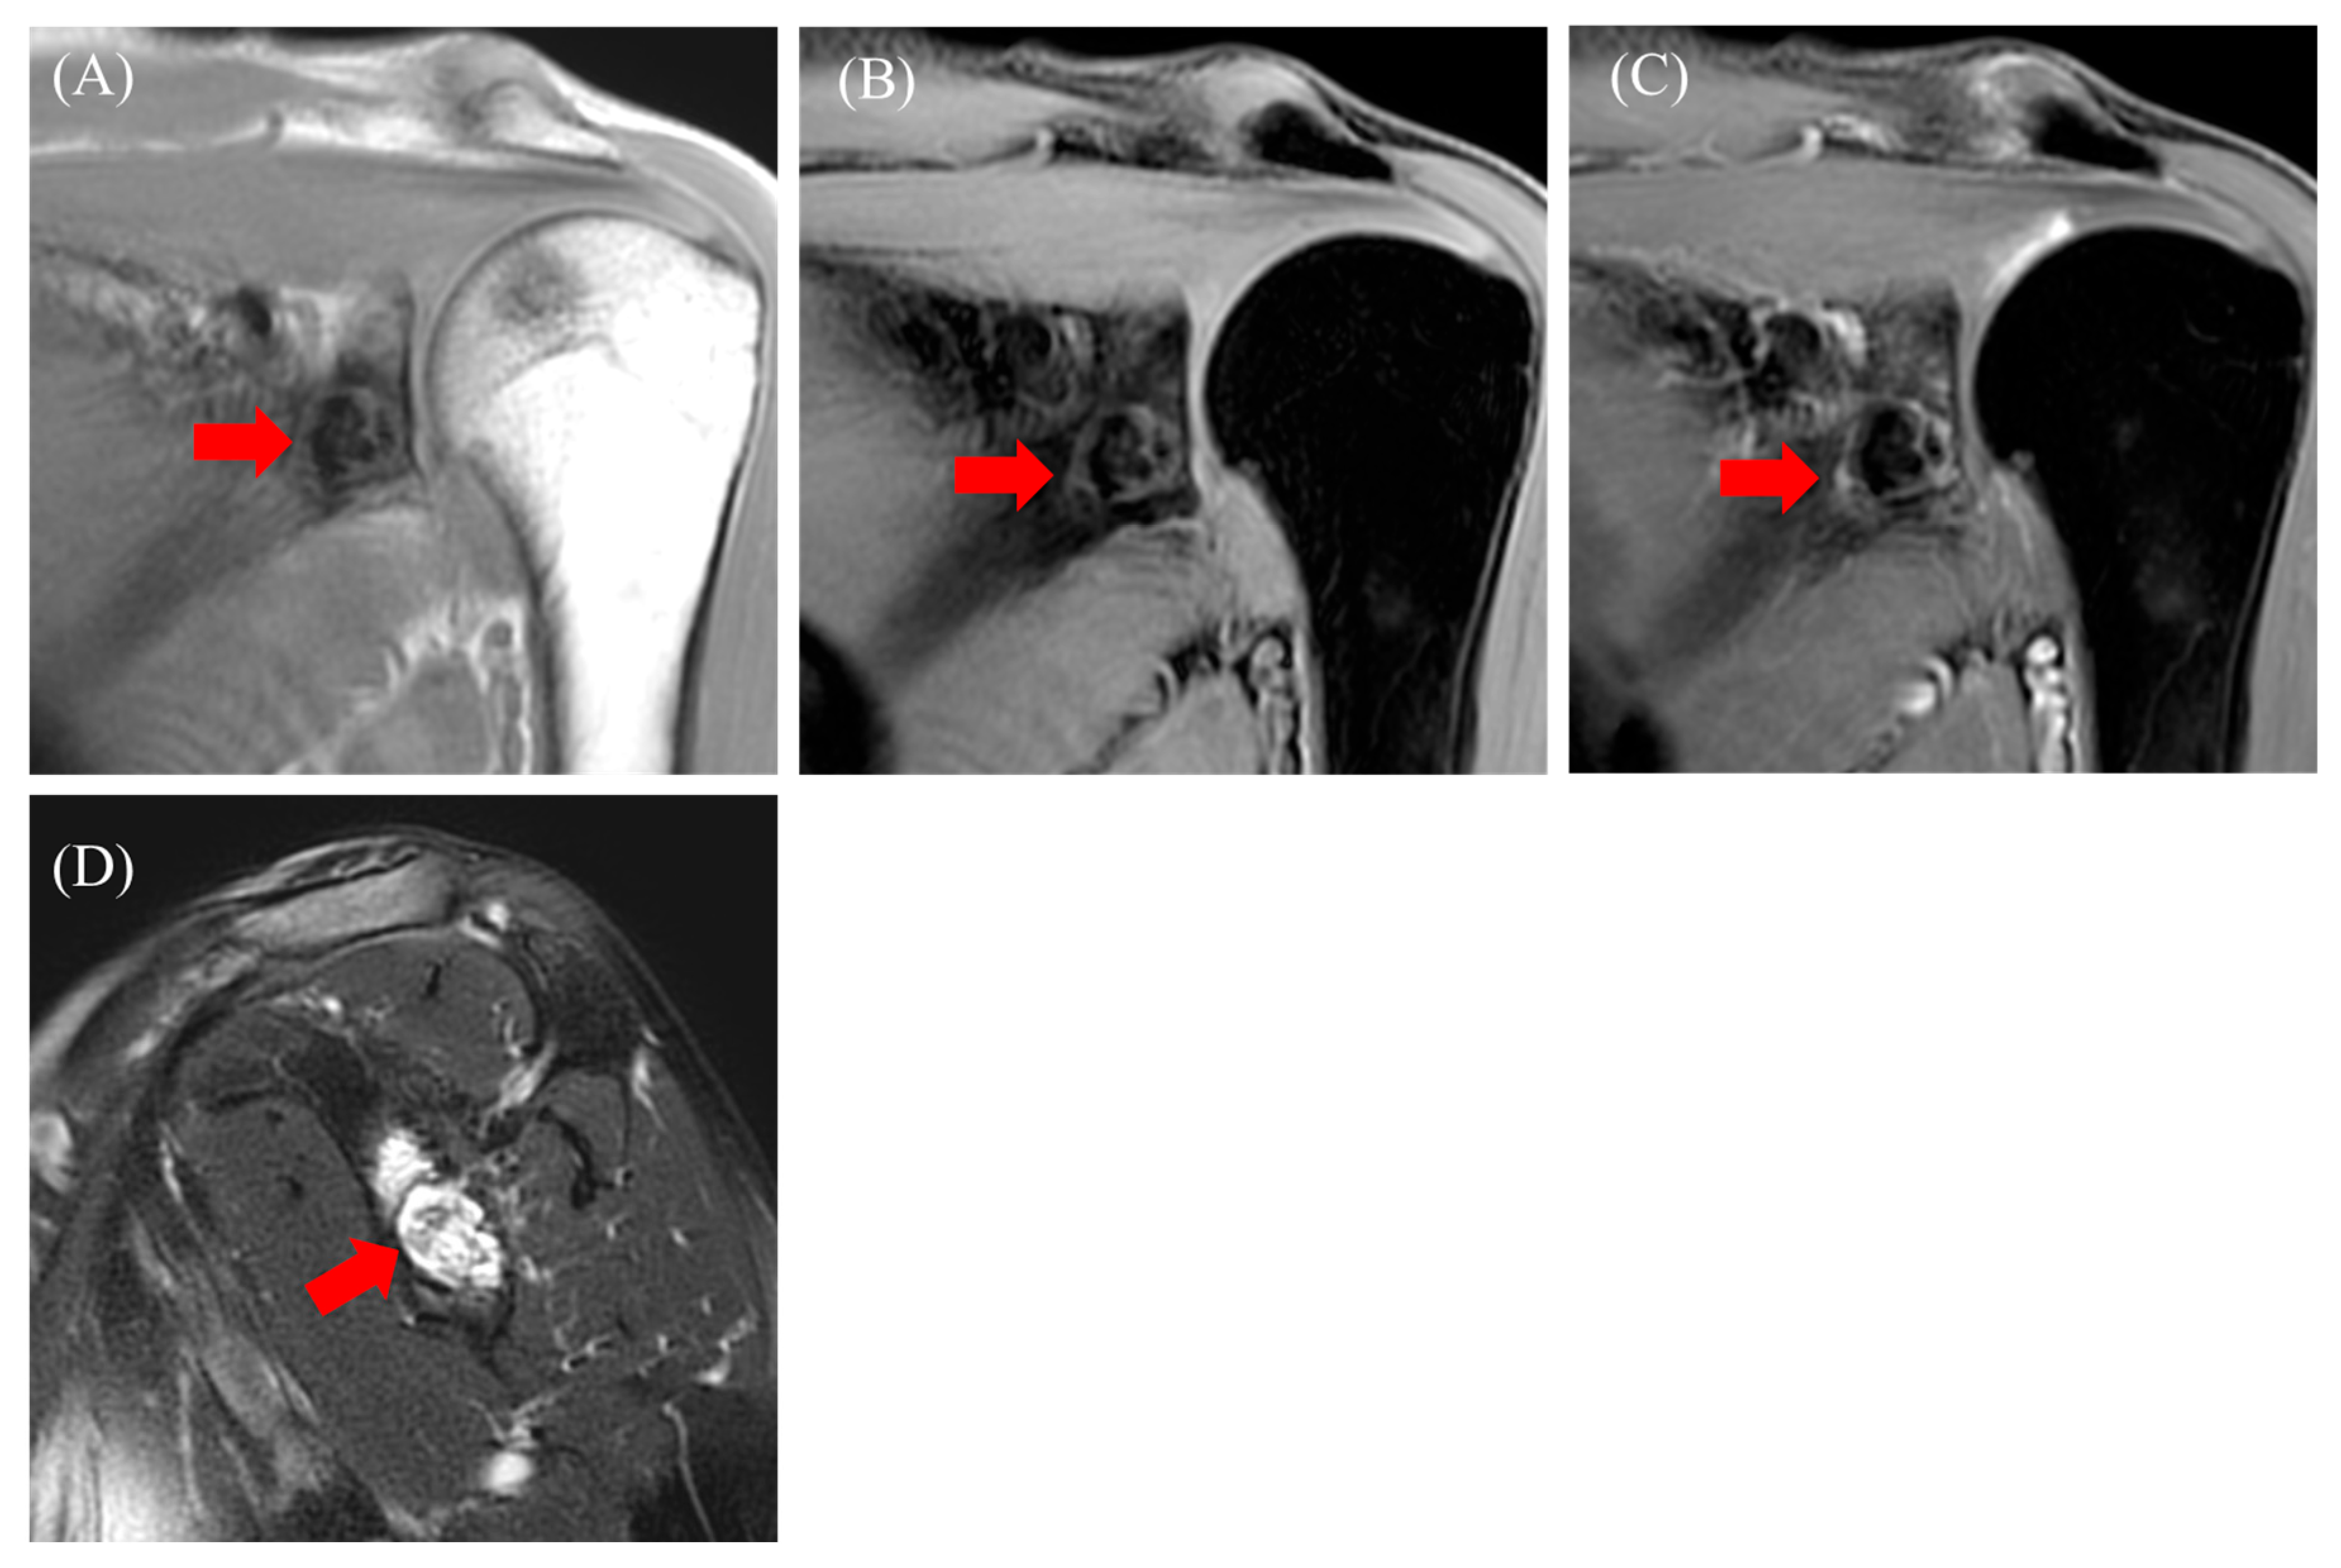

2.1. Case 1